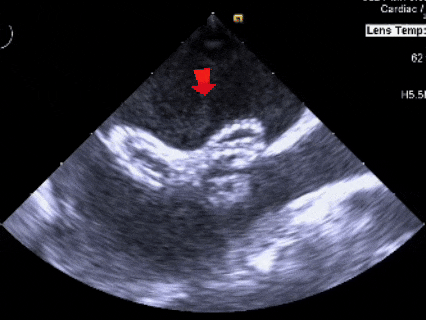

超声下可见封堵器形态良好,封堵成功

释放后评估

彩色多普勒血流成像显示无残余分流存在

封堵成功

释放后多切面下观察

封堵器位置正确、形态良好